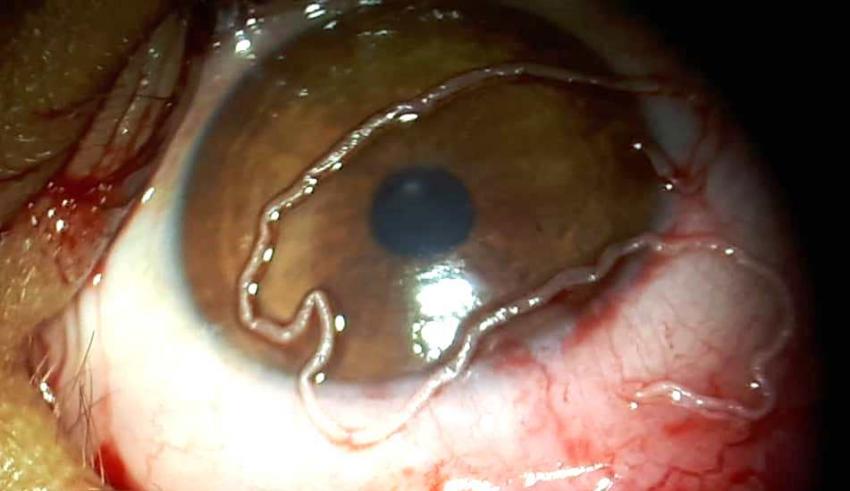

تمكن طاقم طبي تابع لمصلحة طب العيون بمستشفى بوكافر بورزازات، أمس الثلاثاء، من إجراء عملية فريدة من نوعها تمثلت في إستئصال دودة من داخل عين طفل يبلغ من العمر 12 سنة.

تمكن طاقم طبي تابع لمصلحة طب العيون بمستشفى بوكافر بورزازات، أمس الثلاثاء، من إجراء عملية فريدة من نوعها تمثلت في إستئصال دودة من داخل عين طفل يبلغ من العمر 12 سنة.

وأوضحت بديعة عبد اللوي، مندوبة وزارة الصحة بإقليم ورزازات، في تصريح لوكالة المغرب العربي للأنباء، أن العملية الجراحية، التي أشرف عليها رئيس مصلحة طب العيون بالمستشفى، الدكتور سفيان برادي، بمساعدة طاقم شبه طبي ضم 3 ممرضات و ممرضي تخدير، كللت بالنجاح، حيث تم استئصال دودة طولها 10 سم.

وأضافت عبد اللوي أن الطفل، الذي ينحدر من جماعة سكورة (إقليم ورزازات)، أحس بتورم في عينه اليمنى مما استوجب توجيهه الى مستشفى الاختصاصات بوكافر، مضيفة أنه بعد إجراء الفحص السريري و التحاليل الطبية، اتضح ان سبب التورم هو دودة تعيش في عين الطفل، تسمى دودة العين الافريقية.

وأشارت إلى أن عين الطفل لم تتعرض لأي أذى، مضيفة أنه تم إرسال الدودة لمختبر بمراكش للتأكد من نوعها وإخضاعها للمزيد من التحاليل المخبرية.

ويعد هذا المرض من أنواع داء الخيطيات، وينتقل للمريض بعد تعرضه لعضات ذباب الخيل المعروفة أيضا بذبابة المانغو. وينتشر هذا المرض بكثرة في إفريقيا الاستوائية إلا ان حالات الإصابة به في المغرب تبقى نادرة جدا.